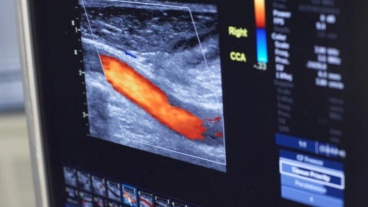

Kathryn Dietmann Bernotavicius, MHA, RVT, has built a career on her training in vascular ultrasound technology - and now helps other Rush graduates follow in her footsteps.